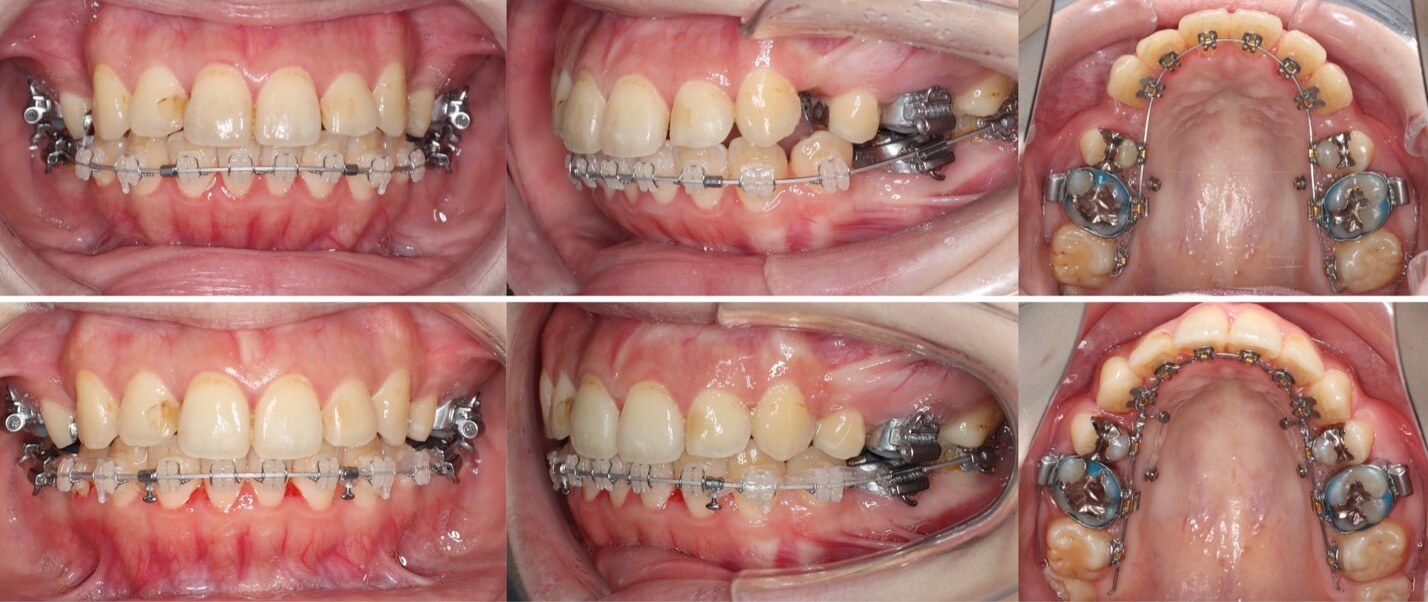

「男性は顔が引き締まる」

高校生男性・唇側矯正装置・下あご後退型

当初は、抜歯矯正治療にするかしないかで、治療方針に迷ったケースですが、最終的には患者さんの希望に沿って抜歯矯正治療にしました。歯の動きがゆっくりであったため、治療期間が3年を超えてしまいました。

<症例概要> 難易度:★★★★☆

主訴:口元の突出・前歯のガタツキ

年齢・性別:高校生男性

住まい:千葉県八千代市市

症状:下顎後退・叢生

治療方針:抜歯空隙の閉鎖(最大固定)

治療装置:唇側矯正装置

固定:歯科矯正用アンカースクリュー(頬側x2)

抜歯:上下第一小臼歯(計4本)

治療期間:3年4か月

リテーナー:上下プレートタイプ+フィックスタイプ

治療費用:968,000(税込)

代表的副作用:痛み・治療後の後戻り・歯根吸収・歯髄壊死・歯肉退縮